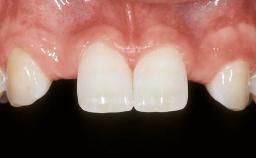

ITI Curriculum FL: Patient Assessment Case 10

Example intended for case-based discussion regarding patient assessment, diagnosis and determination of risk and complexity.

| Patient's Esthetic Expectations | Low | Medium | High |

| Lip Line | No exposure of papillae | Exposure of papillae | Full exposure of mucosa margin |

| Periodontal Phenotype | Low-scalloped, thick | Medium-scalloped, medium-thick | High-scalloped, thin |